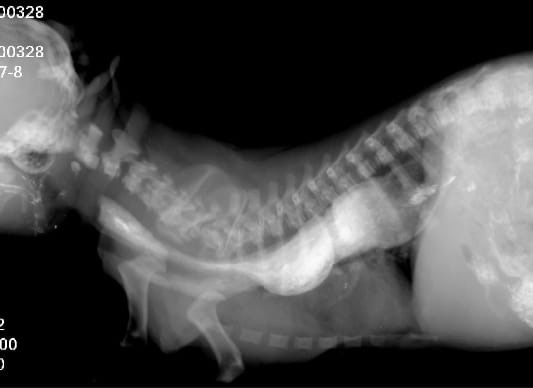

Важно: Мегаэзофагус вызывает именно срыгивание. Если вы видите, что питомец срыгивает непереваренной пищей — это повод для срочной диагностики